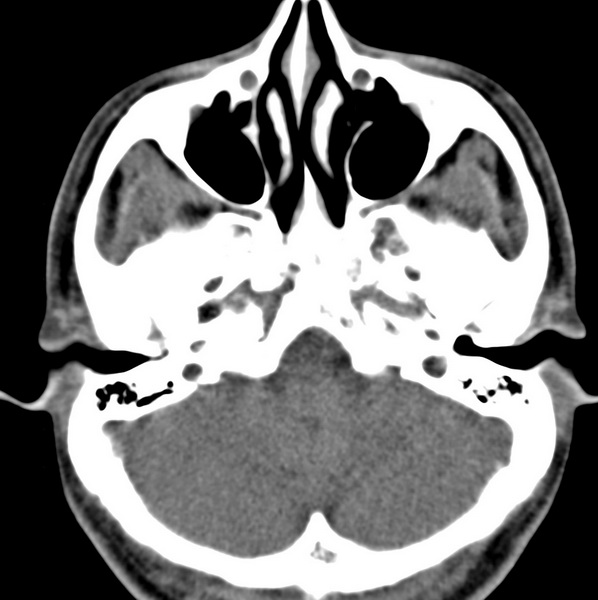

男、31、鼻咽部肿瘤放疗后请帮忙看看。

效果好,右侧破裂孔扩大,局部骨质缺损,为颅底骨质破坏。

1)鼻咽部肿瘤侵犯颅底放疗术后改变。2)左侧蝶窦炎。

咽后壁增厚,左侧咽鼓管隆突增大、咽鼓管咽口变浅,同侧咽旁间隙较窄。右侧颅底骨质破坏?为什么不在同一侧?

鼻咽部肿瘤侵犯颅底放疗术后改变.